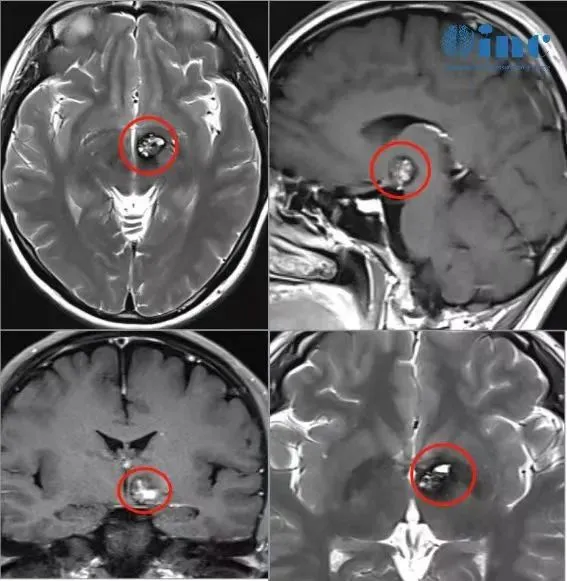

2022年3月,文文首次出现身体异常:双眼向左视物时产生眩晕感。初期认为过度疲劳所致,但症状持续反复。医院检查后确诊为"左侧基底节区海绵状血管瘤伴少量出血",这个诊断结果令患者深感震惊。面对"海绵状血管瘤是否危及生命"的疑问,患者立即前往上海多家知名医院求诊,但均得到"手术风险过大,建议保守观察"的相同建议。

在保守观察期间,患者持续处于焦虑状态。2022年8月,突发剧烈眩晕伴右眼视力急剧下降,MRI检查提示"左侧丘脑基底节占位,海绵状血管畸形合并静脉畸形可能性大"。医疗团队建议药物治疗,半年后复查。2023年初,患者再次出现眩晕和站立不稳症状,复查显示病变略有增大,但手术请求仍被以"手术并发症风险过高"为由拒绝。